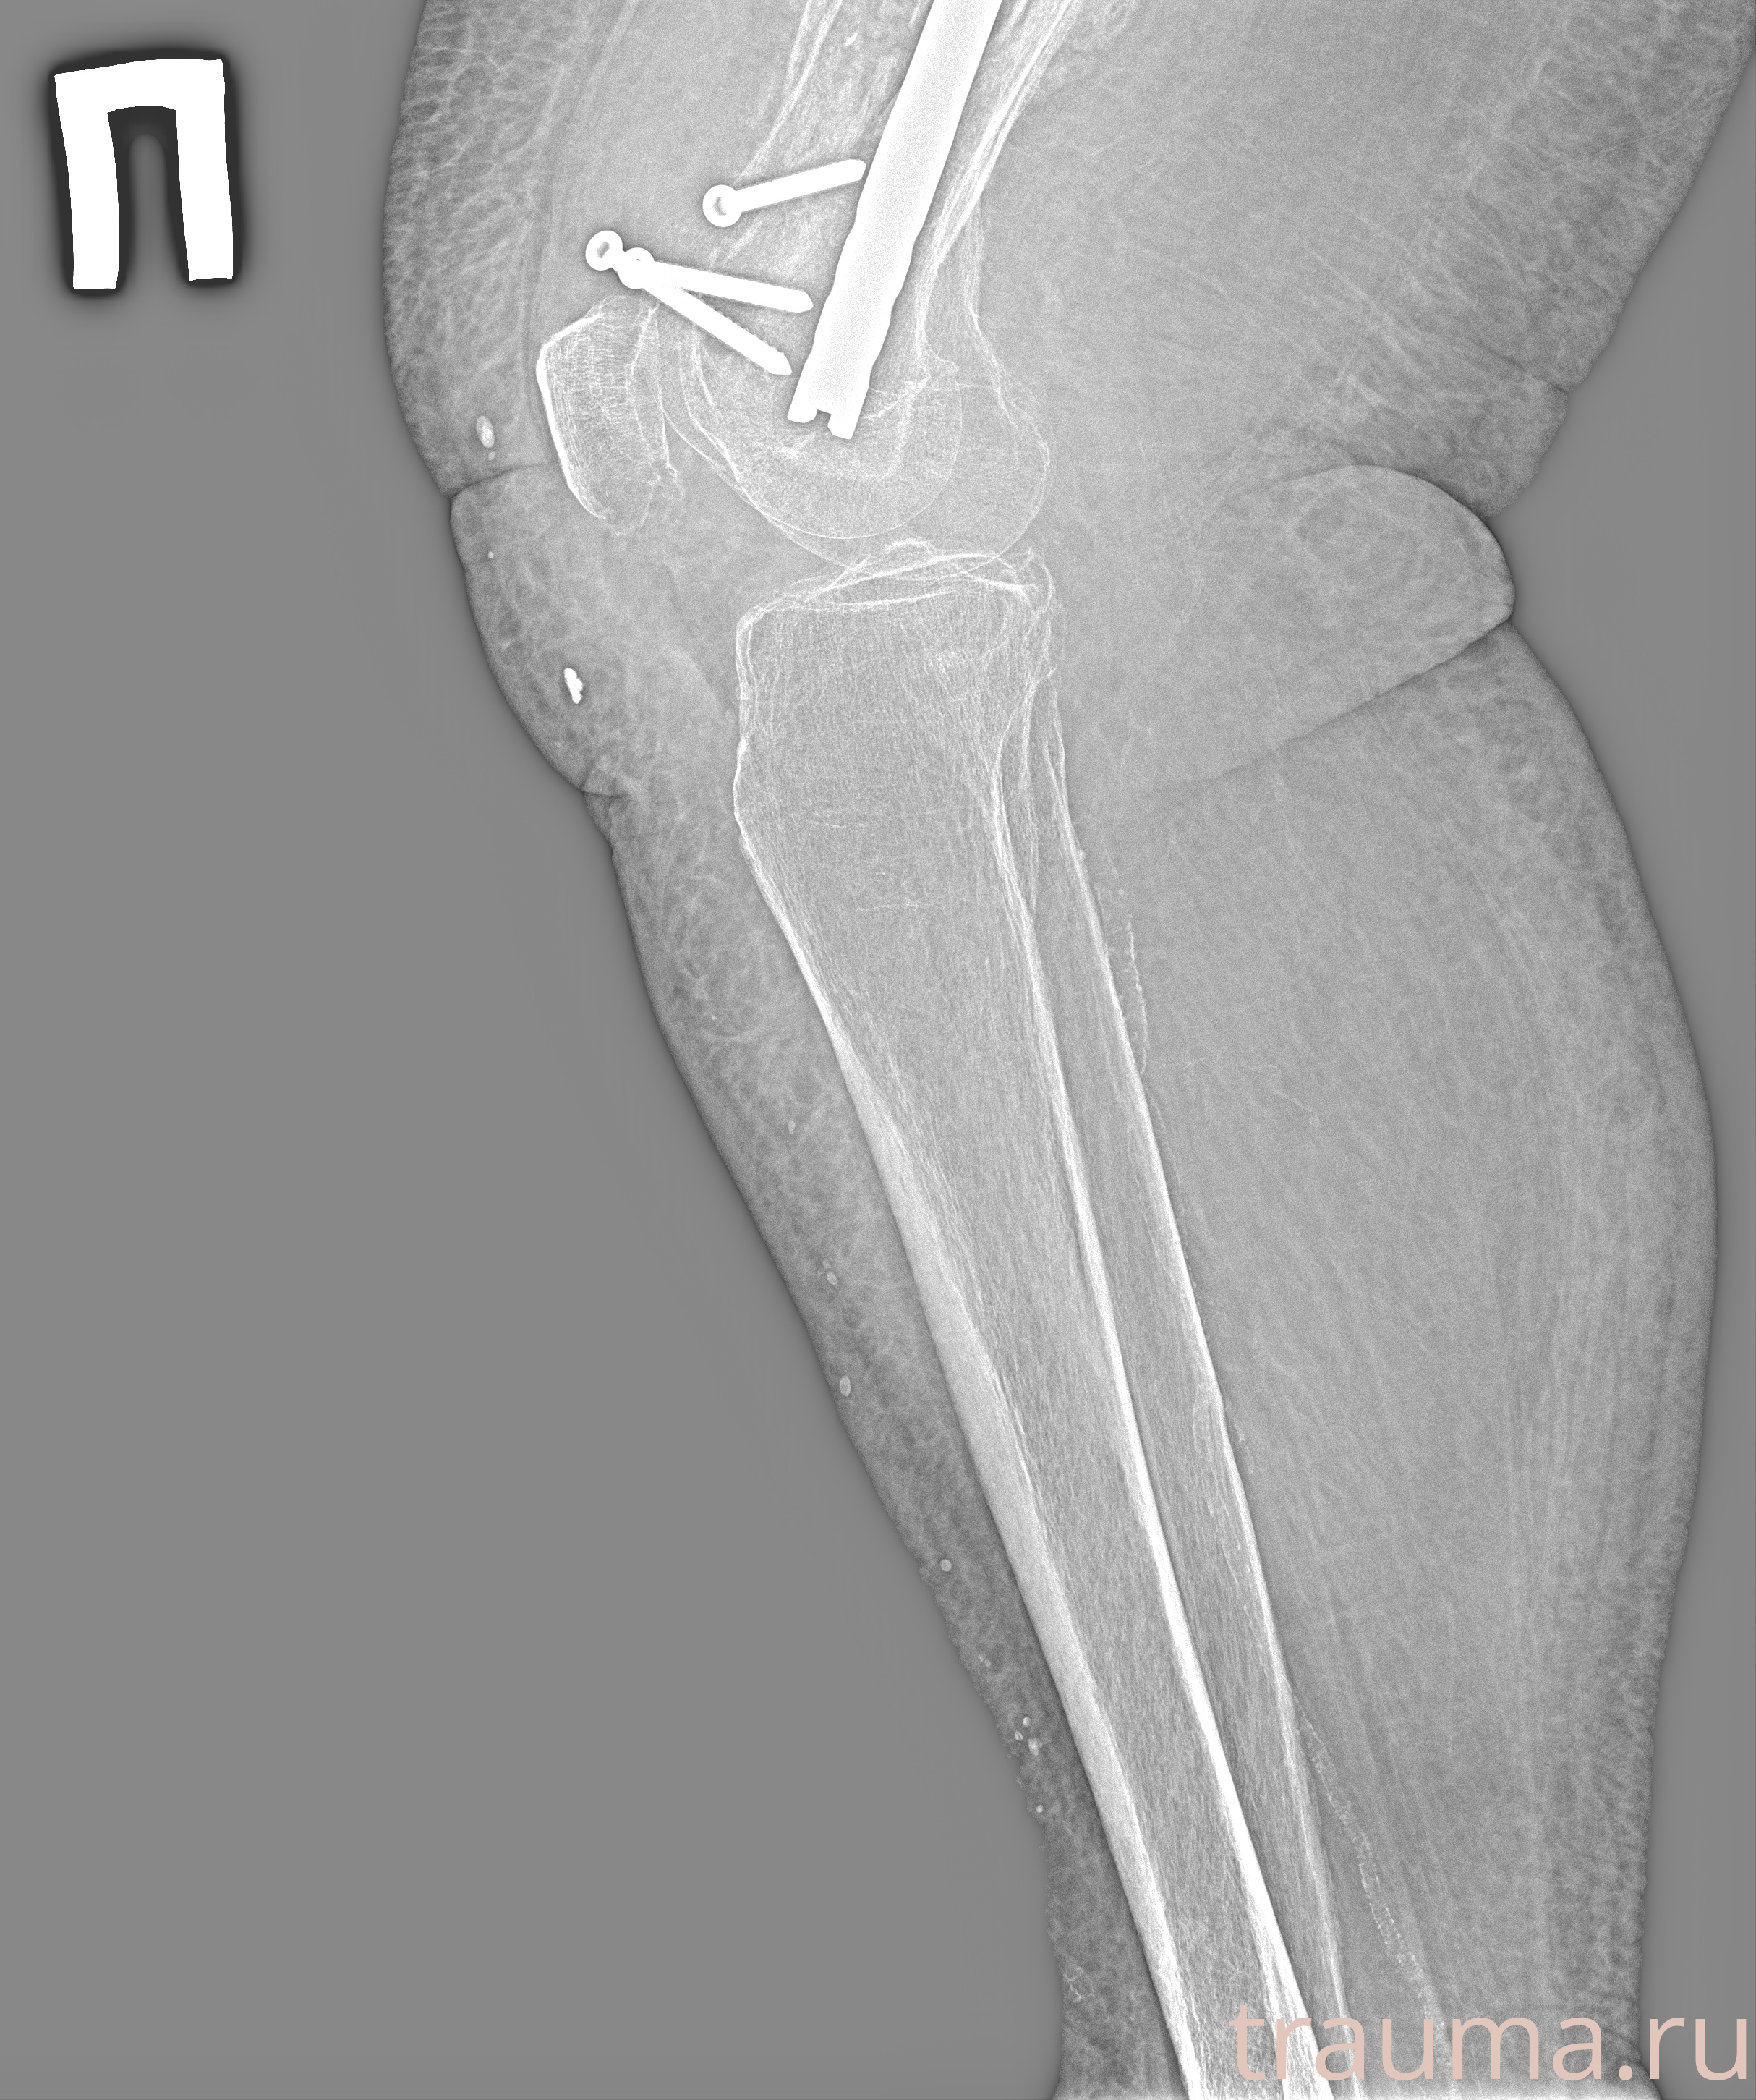

Рентгенограммы

Рентген на дому: по вашему адресу приезжает врач-рентгенолог, травматолог-ортопед с мобильным рентгеновским аппаратом, проводит диагностику травмы или заболевания, делает необходимые рентгенограммы, дает рекомендации по дальнейшему лечению. Получить качественные снимки в домашних условиях возможно благодаря уникальной методике, разработанной МосРентген Центром для института  Склифосовского